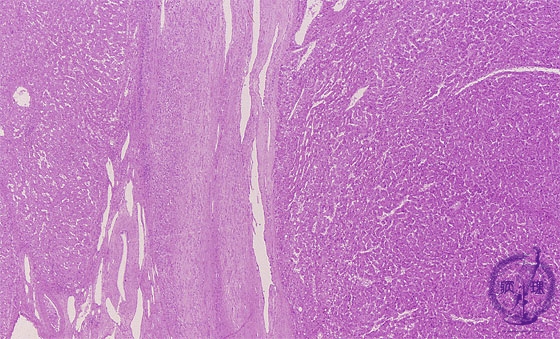

• 10.Liver

• š(12)Hepatocellular carcinoma

Microscopic finding (HE stain, low power view): On the right side is solid type hepatocellular carcinoma. On the left side is the background cirrhotic liver. The two areas are separated by fibrous capsule.

Click the image to see the enlarged image.

• There is no guidance by arrows.